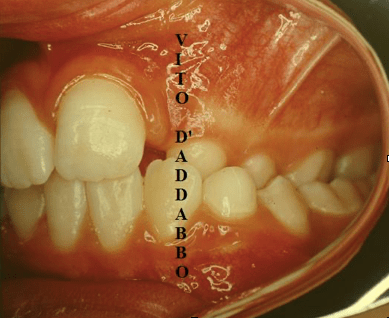

In una bocca che chiude correttamente i denti dell’arcata superiore sono collocati più esternamente rispetto ai corrispondenti dell’arcata inferiore. Nel morso inverso accade il contrario: in quello laterale sono i denti inferiori laterali a chiudere esternamente.

Questa malocclusione è il più delle volte dovuta a un mascellare piccolo, come nel caso riportato, dove manca anche lo spazio per l’incisivo laterale permanente di sinistra. I morsi incrociati vanno corretti precocemente perché possono provocare gravi asimmetrie del viso.

prima